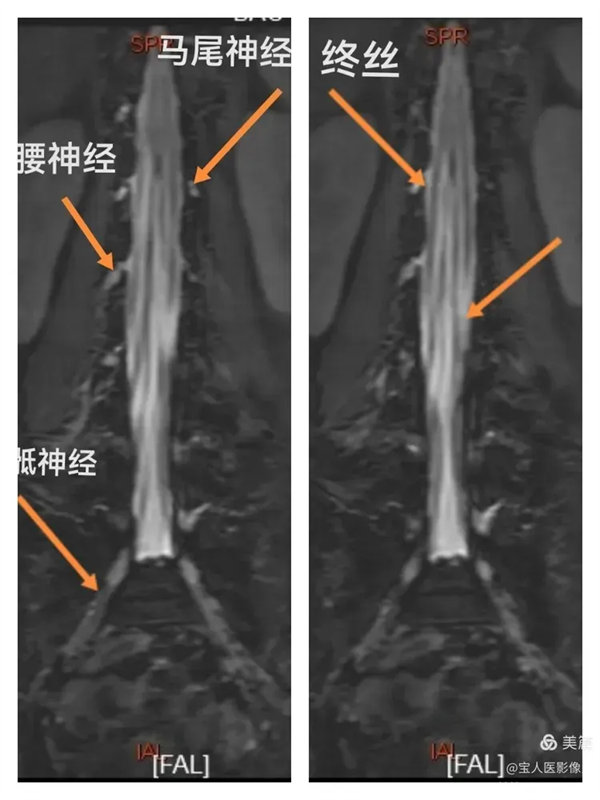

最大密度正面圖,顯示腰段腦脊液(高信號),其內的馬尾神經以及腰神經(線狀稍低信號)。

最大密度正面圖,顯示腰段硬膜囊內腦脊液(高信號),多條終絲、腰神經及骶神經(線狀稍低信號)走行清晰。